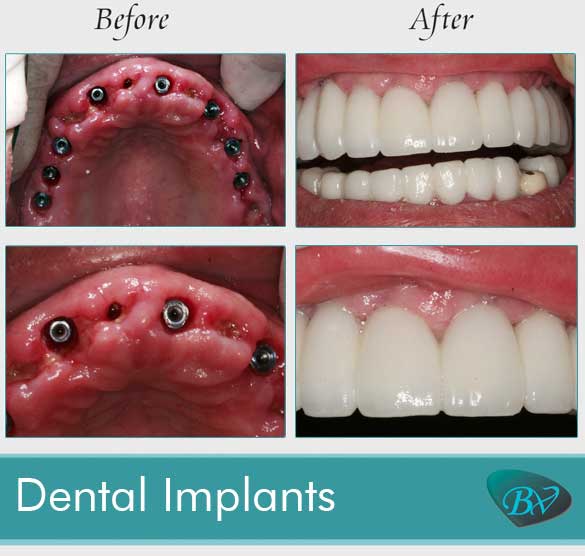

Teeth Implants Before And After – ImplantProTalk.com

Before and after for full arch dental implants. | Dental implants cost …

Before and After Photos of Dental Implants and Cosmetic Dentistry

Before and After: Successful full mouth implants/restoration! – Dental …